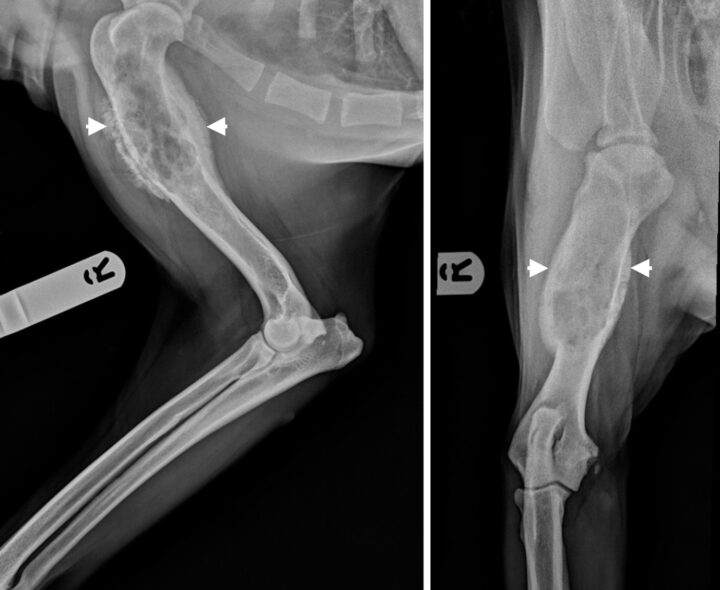

When performing radiographs, orthogonal views should be obtained. Although radiographic features can vary, there is generally evidence of both bony lysis and proliferation; the cortical lysis can be marked and lead to cortical discontinuity. There is often visible soft tissue extension with areas of new bone formation, typically perpendicular to the cortex. Other features include loss of the fine trabecular detail in the metaphysis and a long zone of transition between the normal and affected medullary bone. Figure 1 shows the typical appearance of an OSA.